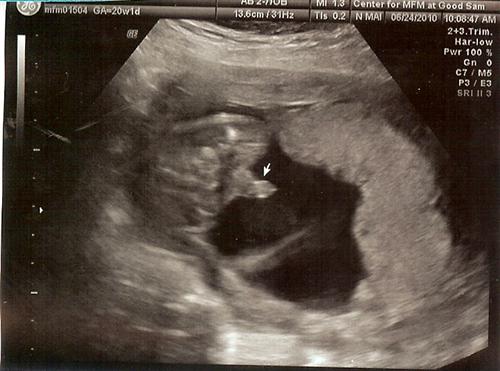

Back from my level 2!!!!!! (with pics)

I would 1st like to thank everyone for their good wishes. Everything is 100% perfect with the baby and it is measuring perfectly from every aspect. Estimated weight is 12ounces so far. They did up my dose of insulin, but are thrilled with how this pregnancy has progressed thus far. The best news is that my cervix has closed!!!

Now here are some pics...

and yes, we caved! It is definitely 100%.......

wow - can't miss that bad boy! yayayayayayayayayay! i love my little nephew - can't wait to hold him

Definetely BOY !!!!

wow totally a boy! hahahaha!!!! Congrats on your little !!!!

And WOW, yes he is a boy. No hiding that one.